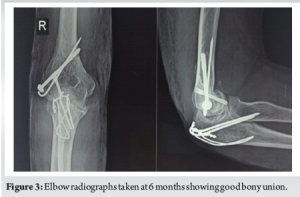

The patient was counseled about the need for surgical intervention for the optimal outcome of the affected joint. Considering the gross swelling, the patient was put on an above-elbow slab, anti-inflammatory drugs for 5 days, and was asked to come back for surgical intervention. The patient was positioned in a left lateral decubitus position. A single standard posterior incision was advocated. The olecranon fracture window was utilized to approach the distal humerus. Appropriate soft tissue dissection and releases were done to approach the second fracture window of the lateral condyle-extensor mass. Indirect reduction of the capitellum was done using bone hooks and fixed with temporary K-wires. Fluoroscopy confirmed anatomical reduction of capitellum fragment, which was later fixed with headless compression screws in posterior to anterior direction. Lateral condyle fixation followed next, which was achieved by means of a K-wire and 4 mm canulated cancellous screw. Finally, the olecranon fracture was fixed by a standard tension band wiring (Fig. 2). The wound was closed in layers, and the elbow was immobilized for the next 10 days in a slab. The patient was followed up at regular intervals of 3 weeks for the initial 3 months and later at interval of 3 months over a 1-year period. Gradual elbow movements were started at 3 weeks, and at the final follow-up (1 year), the patient had a range of 10°–130° elbow flexion. Radiographs showed good bony union with no evidence of arthritic changes (Fig. 3).